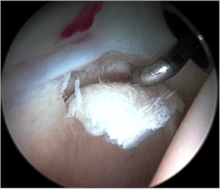

Cam-type femoroacetabular impingement

Cam impingement is created by the abnormal development of the femoral head-neck junction causing what has previously been described as a 'pistol-grip deformity'. This type of deformity is characterised by varying amounts of abnormal bone on the anterior and superior femoral neck at the head-neck junction (see fig. 6). The head-neck junction is at the base of the ball of the hip, where it joins the short neck, which in turn carries on downwards into the femur, or thighbone, itself. A bony protrusion or bump at the head-neck junction has been likened to a cam, an eccentric part of a rotating device. This leads to joint damage as a result of the non-spherical femoral head being forced into the acetabulum mainly with flexion and/or internal rotation. This may impart compression and shear forces to the articular cartilage, and may lead to labral tears and peeling away of the articular cartilage from the underlying bone, so-called cartilage delamination (see fig. 8).[9][10]

Standard arthroscopic treatment of symptomatic cam FAI involves debridement (resection) or repair of any labral [10] and chondral injuries [11] in the central compartment of the hip, and subsequent reshaping of the head-neck junction of the upper femur (osteochondroplasty) in the peripheral compartment [12][13] using high-speed motorised burrs that are similar in design to a dentist's drill (see fig. 9).